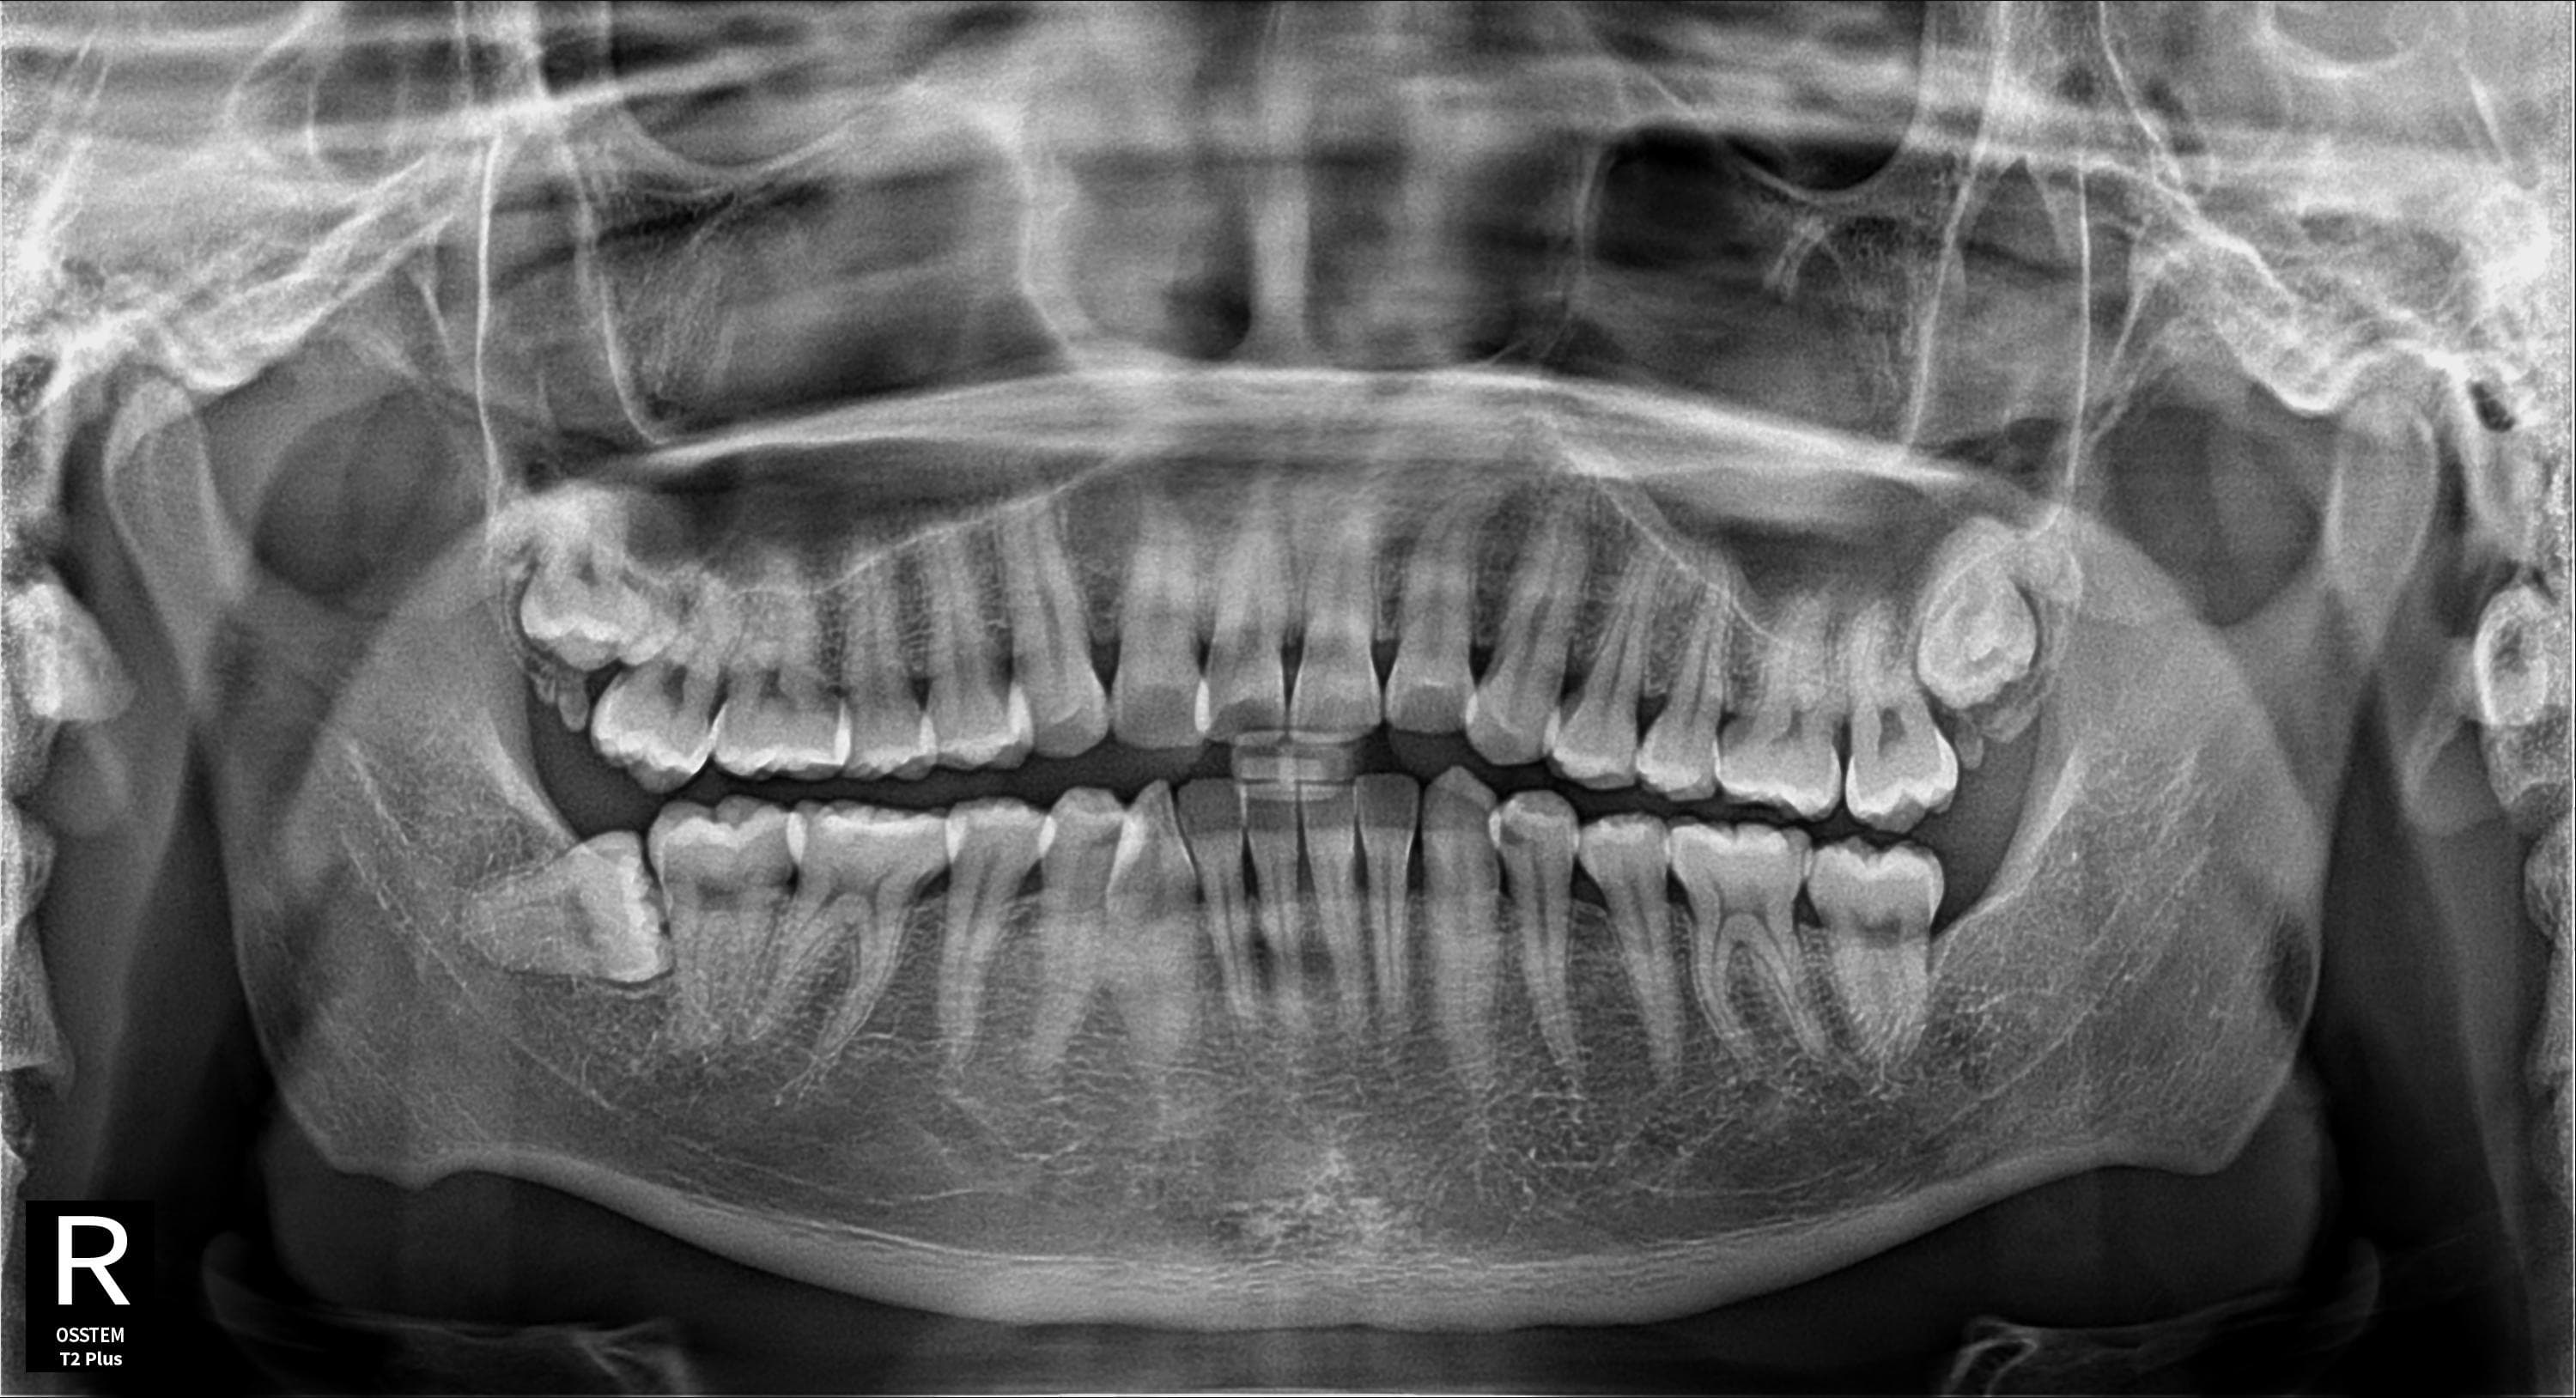

왼쪽 아래 사랑니 발치

왼쪽 아래 매복 사랑니 안전 발치

Before

After

매복된 왼쪽 아래 사랑니를 안전하게 발치 완료